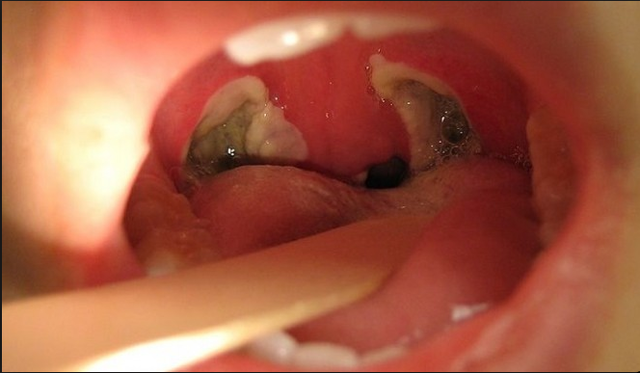

• When I got my tonsils cut out.

When I got my tonsils cut out.

On september 13 was the day I got my tonsils taken out. It was a very painful experience. lol....This photo I picked is nt my mouth but this is what my mouth looked like with the scar tissue still healing. I found it on google images